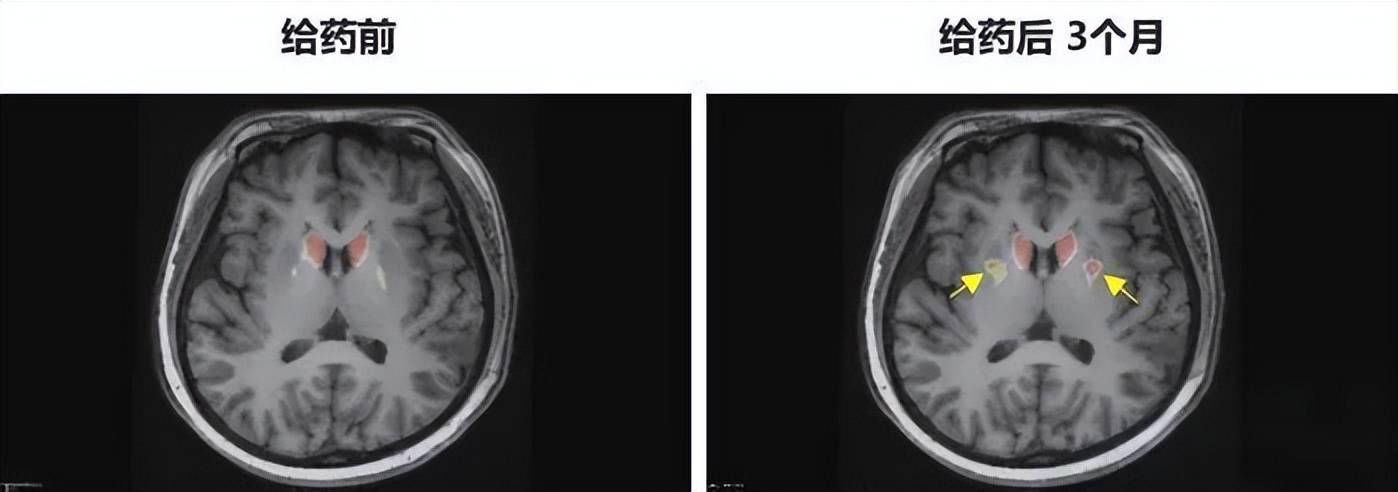

▲ PET-DAT/MRI融合图像术前与术后三个月对比

手术非常成功,奇迹也随之发生。术后的前两个月,李女士静止性震颤、僵直等症状明显减轻,帕金森病评定量表得分从术前62分(重度功能障碍)逐渐降至28分。到了9月上旬,李女士的“关期”完全消失,量表评分降至12分,基本接近常人,每日是否服用既往药物已无明显差异。影像学评估显示,全新的多巴胺能神经元在她的大脑中成功定植、发挥活性,标志着初步实现了功能性治愈。